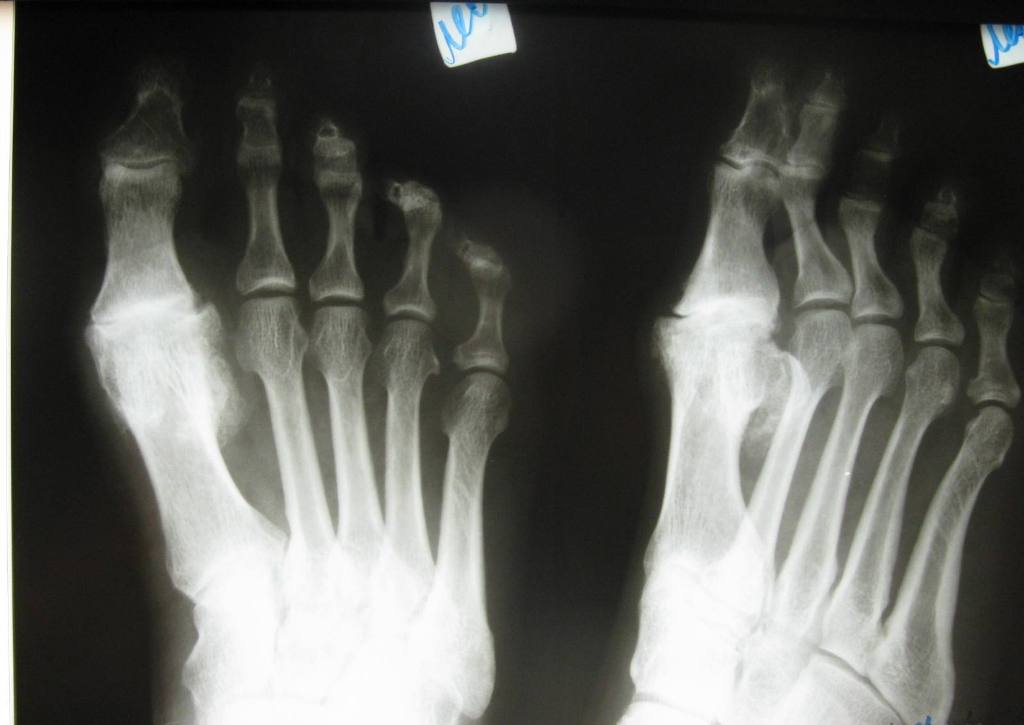

Рентгеновские снимки анкилоза суставов: Как это выглядит